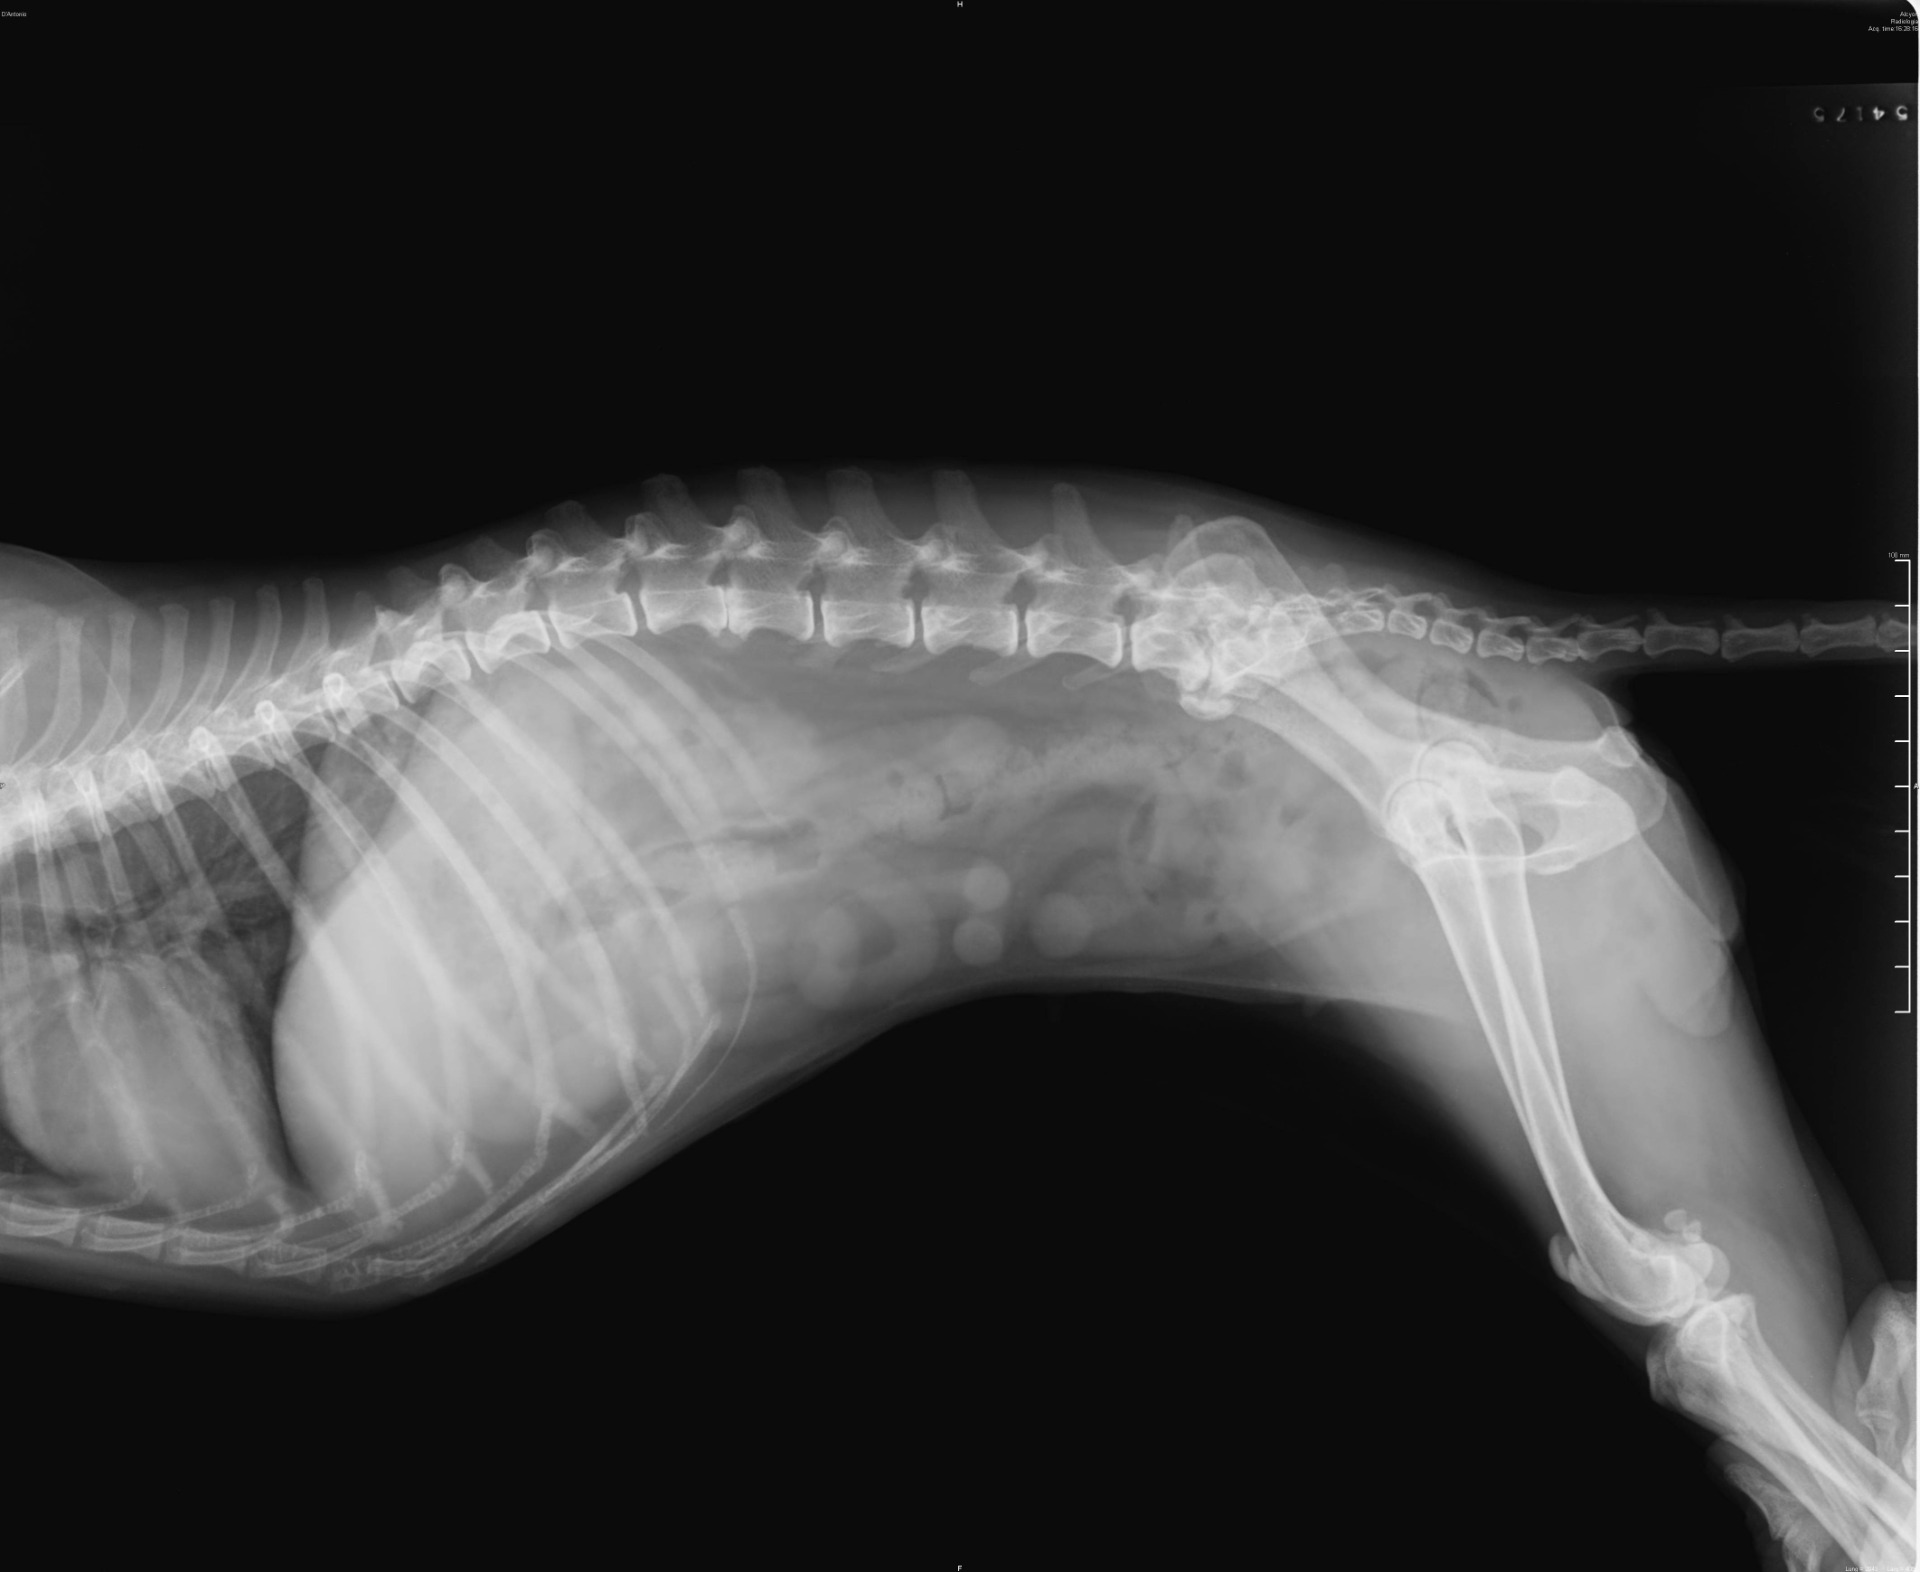

RENTGEN